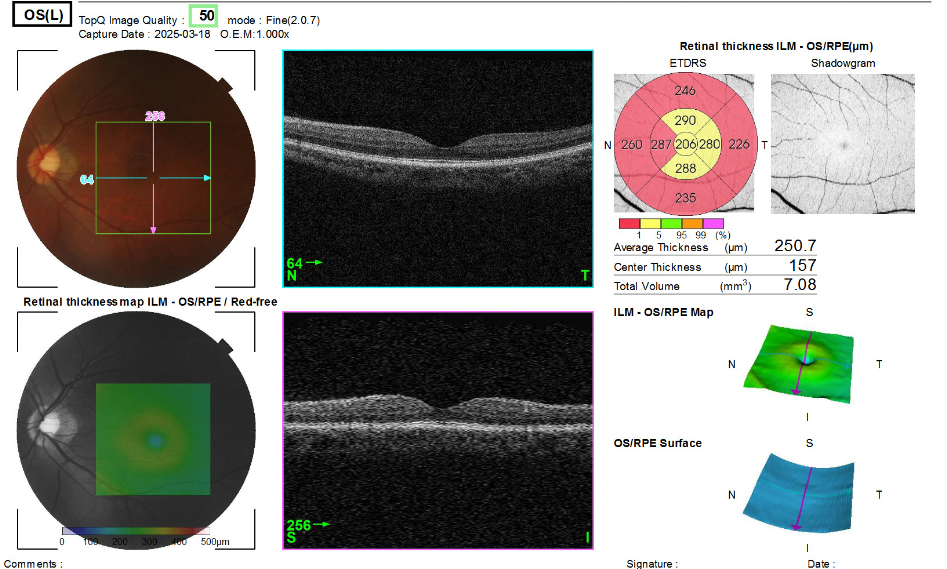

왼쪽 OCT 촬영결과

왼쪽눈은 전형적인 정상안의 결과를 보인다.